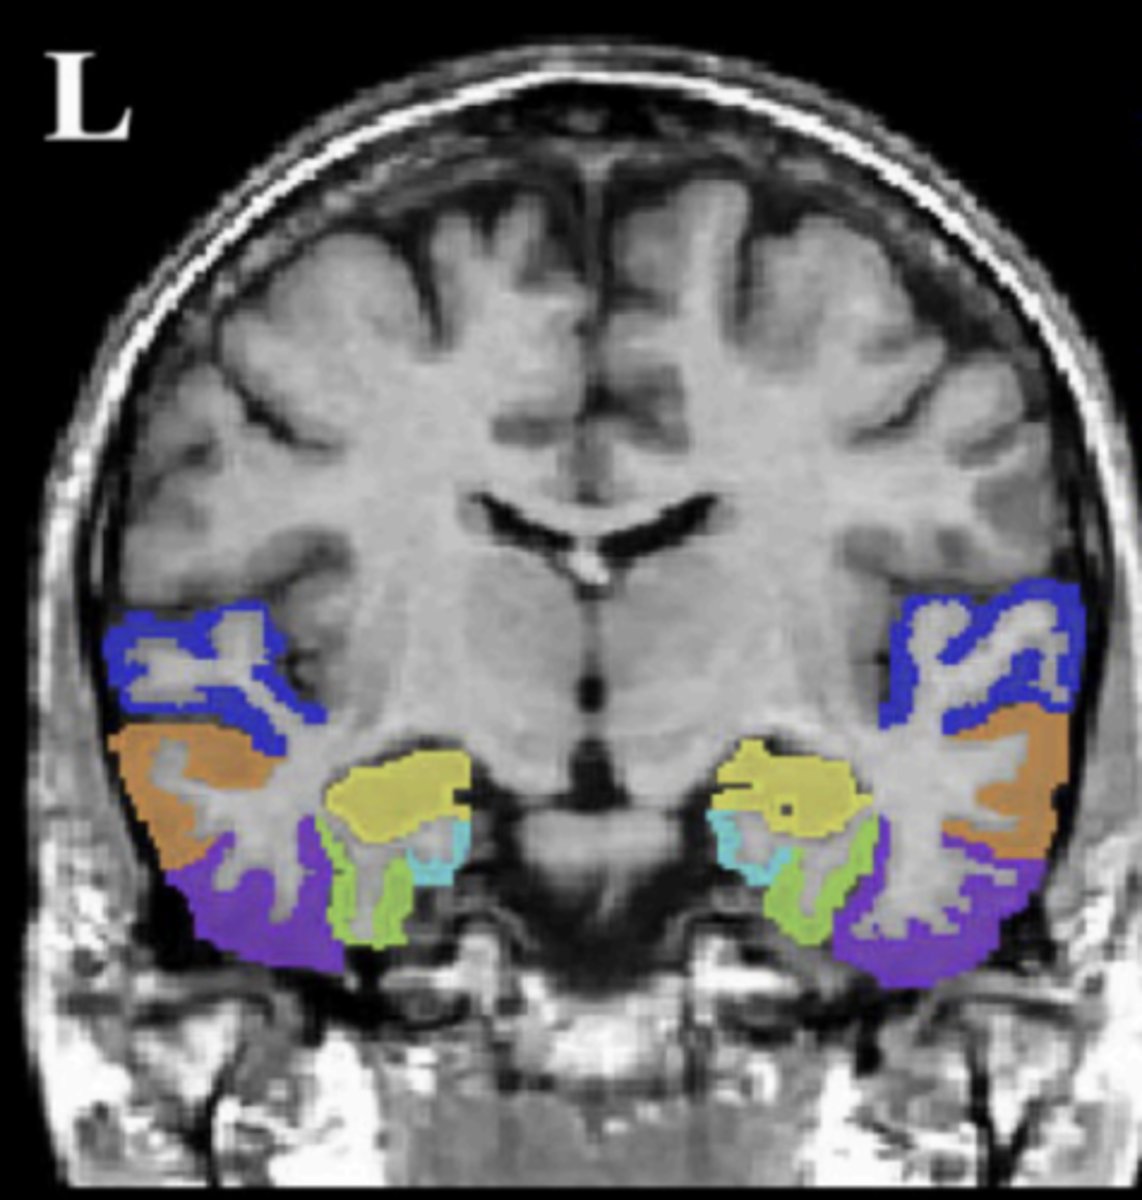

temporal lobe (coronal view)

superior temporal gyrus (STG)

dark blue area

middle temporal gyrus (MTG)

orange area

inferior temporal gyrus (ITG)

purple area

fusiform gyrus (FG)

green area

parahippocampal gyrus (PHG)

light blue area

hippocampus (HIPP)

yellow area